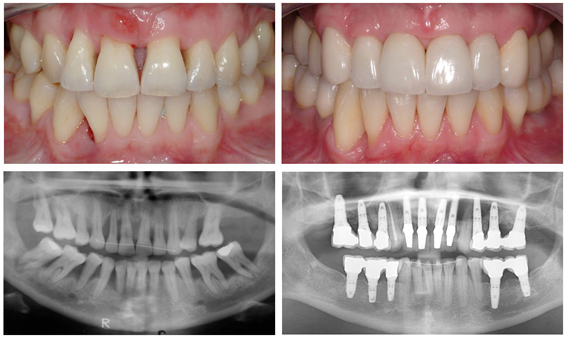

Gum Treatments

Gum disease is an infection of the tissues that surround and support your teeth. It is a major cause of tooth loss in adults. Because gum disease is usually painless, you may not know you have it. Also referred to as periodontal disease, gum disease is caused by plaque, the sticky film of bacteria that is constantly forming on our teeth.